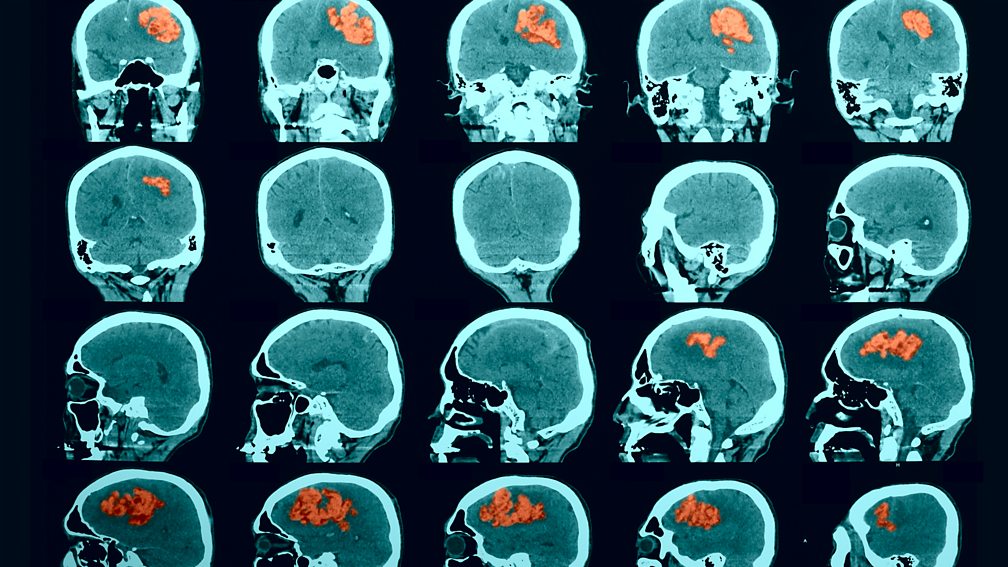

Brain Bleed Brain Bleed On Ct How Do I Know If I Have A Brain Bleed After A Fall A subdural hematoma is a type of bleeding near your brain that can happen after a. — the signs and symptoms of mild traumatic brain injury may include: A person with a bleed on the brain may experience a sudden severe headache. — the signs and symptoms of traumatic brain injury that have resulted from head trauma may. How Do I Know If I Have A Brain Bleed After A Fall.